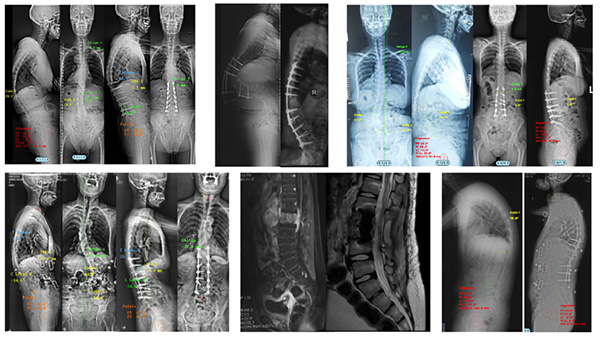

本中心以精湛的医疗技术和丰富的临床经验著称,所治疗的疾病种类覆盖了退行性变、肿瘤、先天畸形和慢性疼痛等几乎全部脊柱脊髓疾病。在常见脊柱脊髓疾病如颈椎病、腰椎病、椎管内肿瘤、脊髓空洞及慢性疼痛等的诊治中,秉持微创与安全理念,以显微镜、内镜、经皮通道等显微外科技术为引领,为患者提供安全有效的治疗方案。同时,本中心在高难度手术领域成果斐然,经口齿状突切除技术、显微镜下颈椎后纵韧带骨化前路椎管扩大技术(ACAF技术)、基于OLIF的脊柱畸形矫形、脊柱肿瘤(en bloc)切除联合3D打印椎体重建、髓内肿瘤、前路肠源性囊肿切除、脊髓与周围神经电刺激、脊柱畸形矫形技术以及脊柱截骨治疗脊髓拴系等复杂手术已成为常规操作,相关手术技术和开展例数在国内均处于领先地位。本中心医师创新性提出直接后路寰枢关节松解复位技术(PFDF技术)、微创蛛网膜下腔-蛛网膜下腔脑脊液搭桥术、时序脊髓电刺激联合外骨骼治疗等新技术,获得国际声誉。

高精尖手术